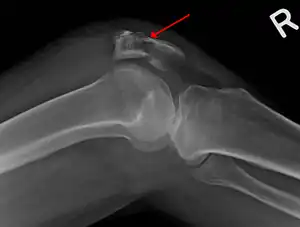

The patella can break in various ways depending on the way it is injured, and into two or more pieces.[1] Types include transverse, with one fracture line and is the most common type,[5] marginal, osteochondral and the rare vertical type, or stellate, where a direct compression force gives rise to a comminuted pattern.[5][7] Patella fractures can be further classified as displaced, where the broken ends of bone do not line up correctly and separate by more than 2mm, or undisplaced and stable where pieces of bone remain in contact with each other.[1][7] If fragments of patella bone stick out from the skin it is known as an open patella fracture, and closed if the overlying skin is intact.[1]

Transverse fracture of patella -

Comminuted fracture of patella -

Osteochondral fracture of patella -

Vertical patella fracture